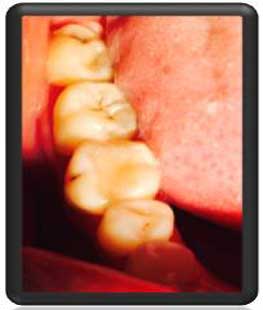

بعد از بستن قالب مخصوص voco حفره توسط کامپوزیتآلمان پرشد |